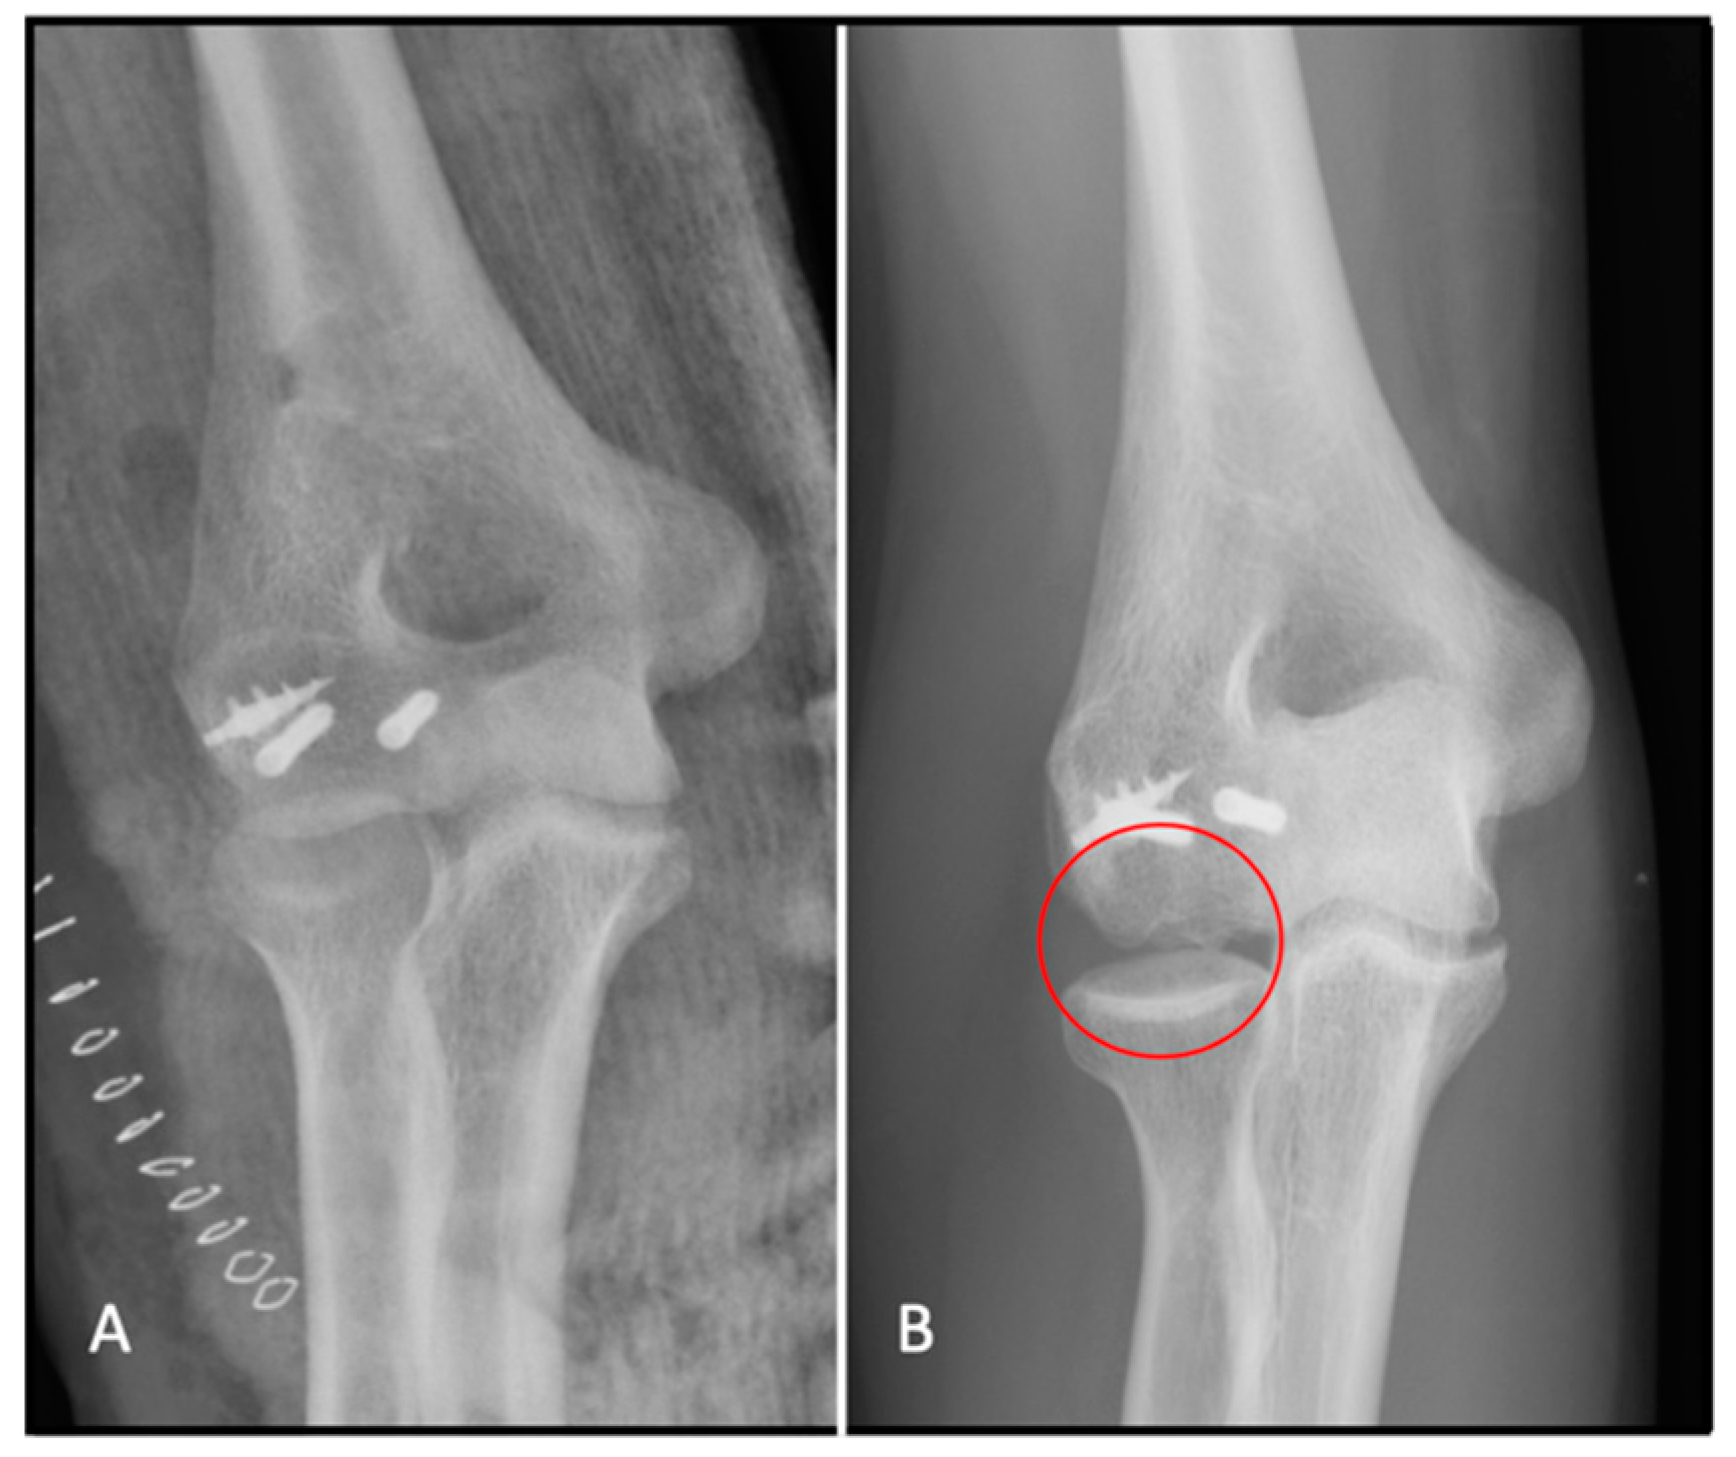

4.7.1. Isolated Screw Fixation

4.7.2. Kirschner Wires

4.7.3. Plates